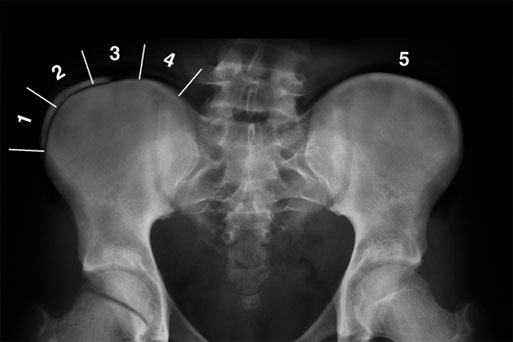

2.脱位分型:以髂坐线(Nelaton:坐骨结节至髂前上棘的连线。正常情况下,此线经过大转子尖端,当股骨颈骨折或髋关节后脱位时,大转子尖端可向上移位超过此线。)为标准:前方——前脱位(外展位);后方——后脱位(内收位);中心脱位:股骨头突破髋臼底部或入盆腔(合并有髋臼横行骨折,或髋臼顶骨折或者髋臼复杂性骨折,并入髋臼骨折处理)

沈通氏线(Shenton’s线):是指正常骨盆X线中耻骨下缘弧形线与股骨颈内侧弧形线连成的弧度。